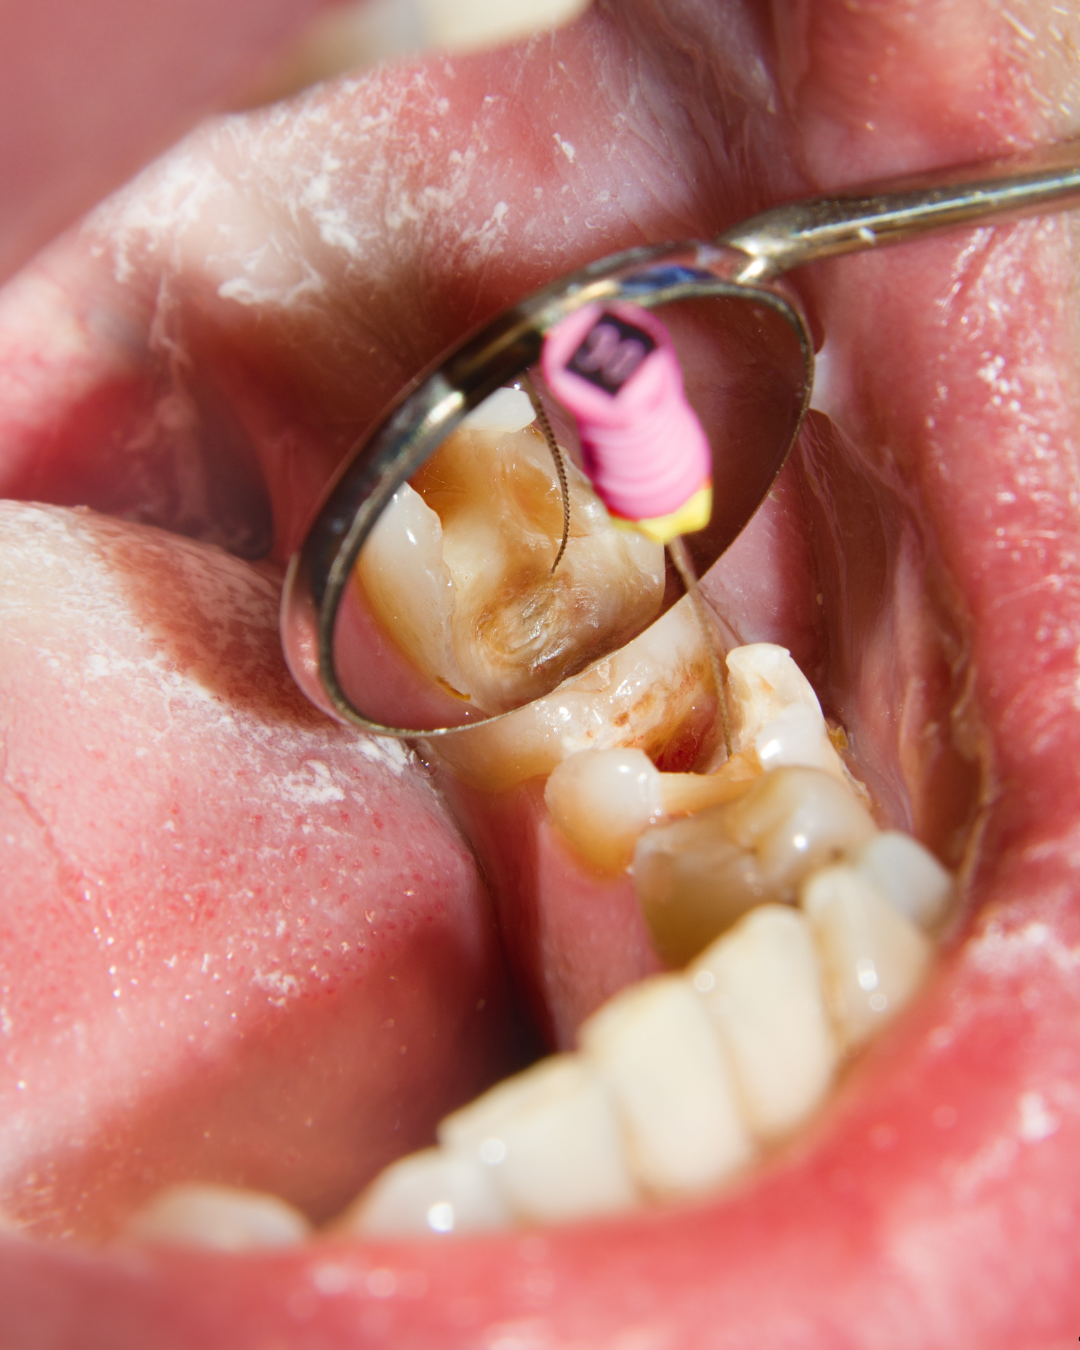

This on-demand online course introduces fundamental protocols of endodontic therapy. Content includes diagnosis, working length determination, canal instrumentation principles, irrigation techniques, obturation methods, and restorative considerations following endodontic treatment illustrated through procedural demonstrations.